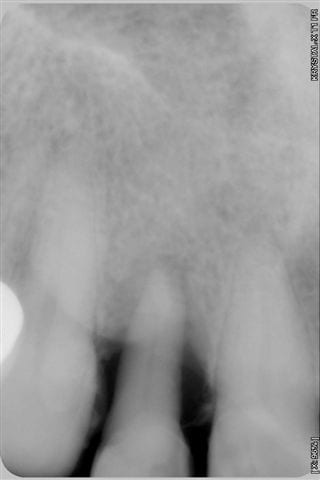

Souvenez vous, il y a 6 mois, je vous ai posté des photos sur un cas de parodontopathie aiguë localisée à la 12, voici les photos et radio 6 mois plus tard, après traitement de la paro au laser diode 980 nm sous bipivone puis H2O2, bio stimulation tous les 15 jours et reconstruction de la couronne en emax avec le CEREC 6 mois plus tard.

- Dommage que les radios ne soient pas indexées avec leur date, car avec le désordre dans lequel le serveur les met, c'est un peu plus difficile de suivre l'évolution de la guérison (qui n'est pas encore complète apparemment).